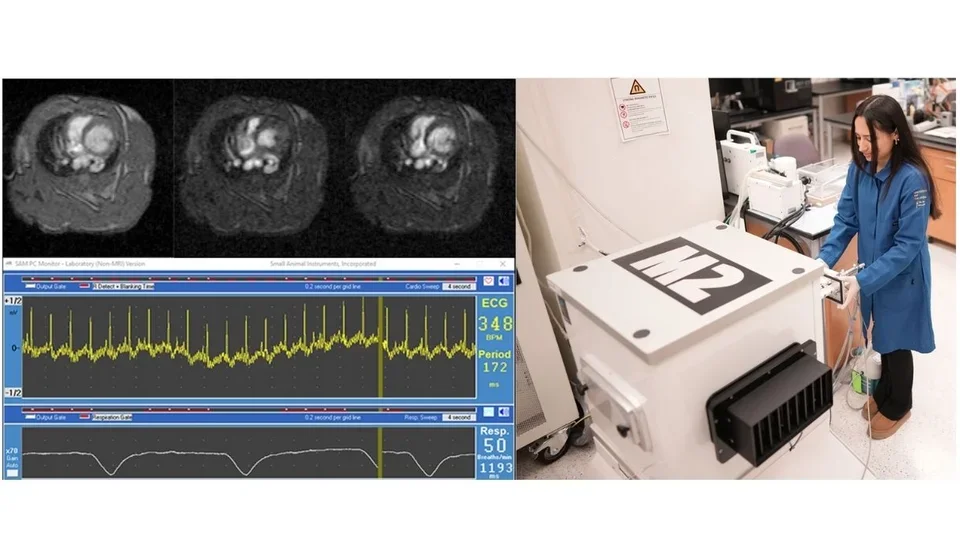

Magnetic resonance imaging (MRI), originally called nuclear magnetic resonance imaging (NMRI), is an imaging technique used to form pictures of the anatomy and the physiological processes of the body. MRI scanners use strong magnetic fields, magnetic field gradients, and radio waves to generate images of organs in the body. Because certain atomic nuclei are able to absorb radio frequency energy when placed in an external magnetic field, the resultant evolving spin polarization can induce a RF signal in a radio frequency coil and thereby be detected. Hydrogen atoms are naturally abundant in biological organisms, particularly in water and fat. For this reason, MRI scans essentially map the location of water and fat in the body. Pulses of radio waves excite the nuclear spin energy transition, and magnetic field gradients localize the polarization in space. By varying the parameters of the pulse sequence, different contrasts may be generated between tissues based on the relaxation properties of the hydrogen atoms therein. Compared to CT, MRI provides better contrast in images of soft-tissues, e.g. in the brain or abdomen. Our Aspect 1T M2 MRI has a spatial resolution of 156 micron, and can perform ECG-gated imaging of cardiovascular and respiratory systems.

M2 MRI for mice and rats (Aspect Imaging)